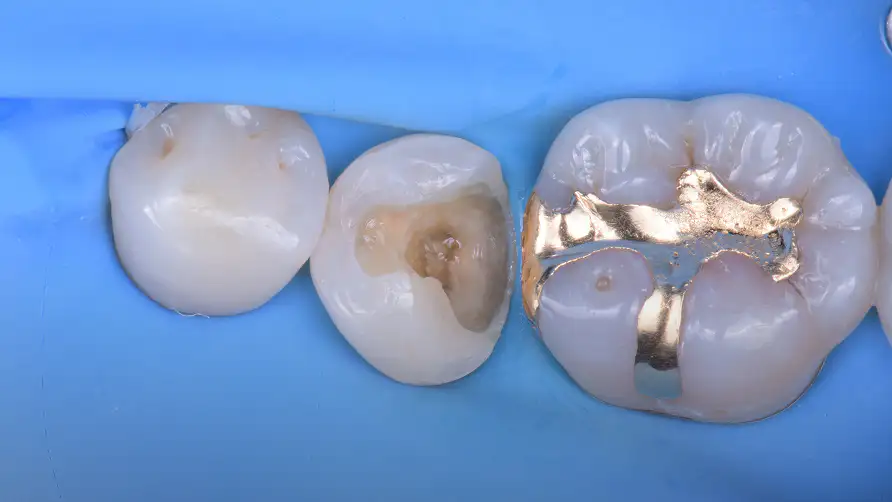

해부학적 형태의 정밀 복원

간접 수복은 구강 외에서 수작업으로 보철물을 제작합니다. 정교하게 치아의 해부학적인 형태를 복원하고, 교합 관계를 회복시킵니다.

오차를 최소화하는 정밀한 보철 과정

정밀하게 제작된 보철물은 경계부에서의 오차를 최소화하고, 내면의 적합을 최대화하는 방향으로 제작됩니다.